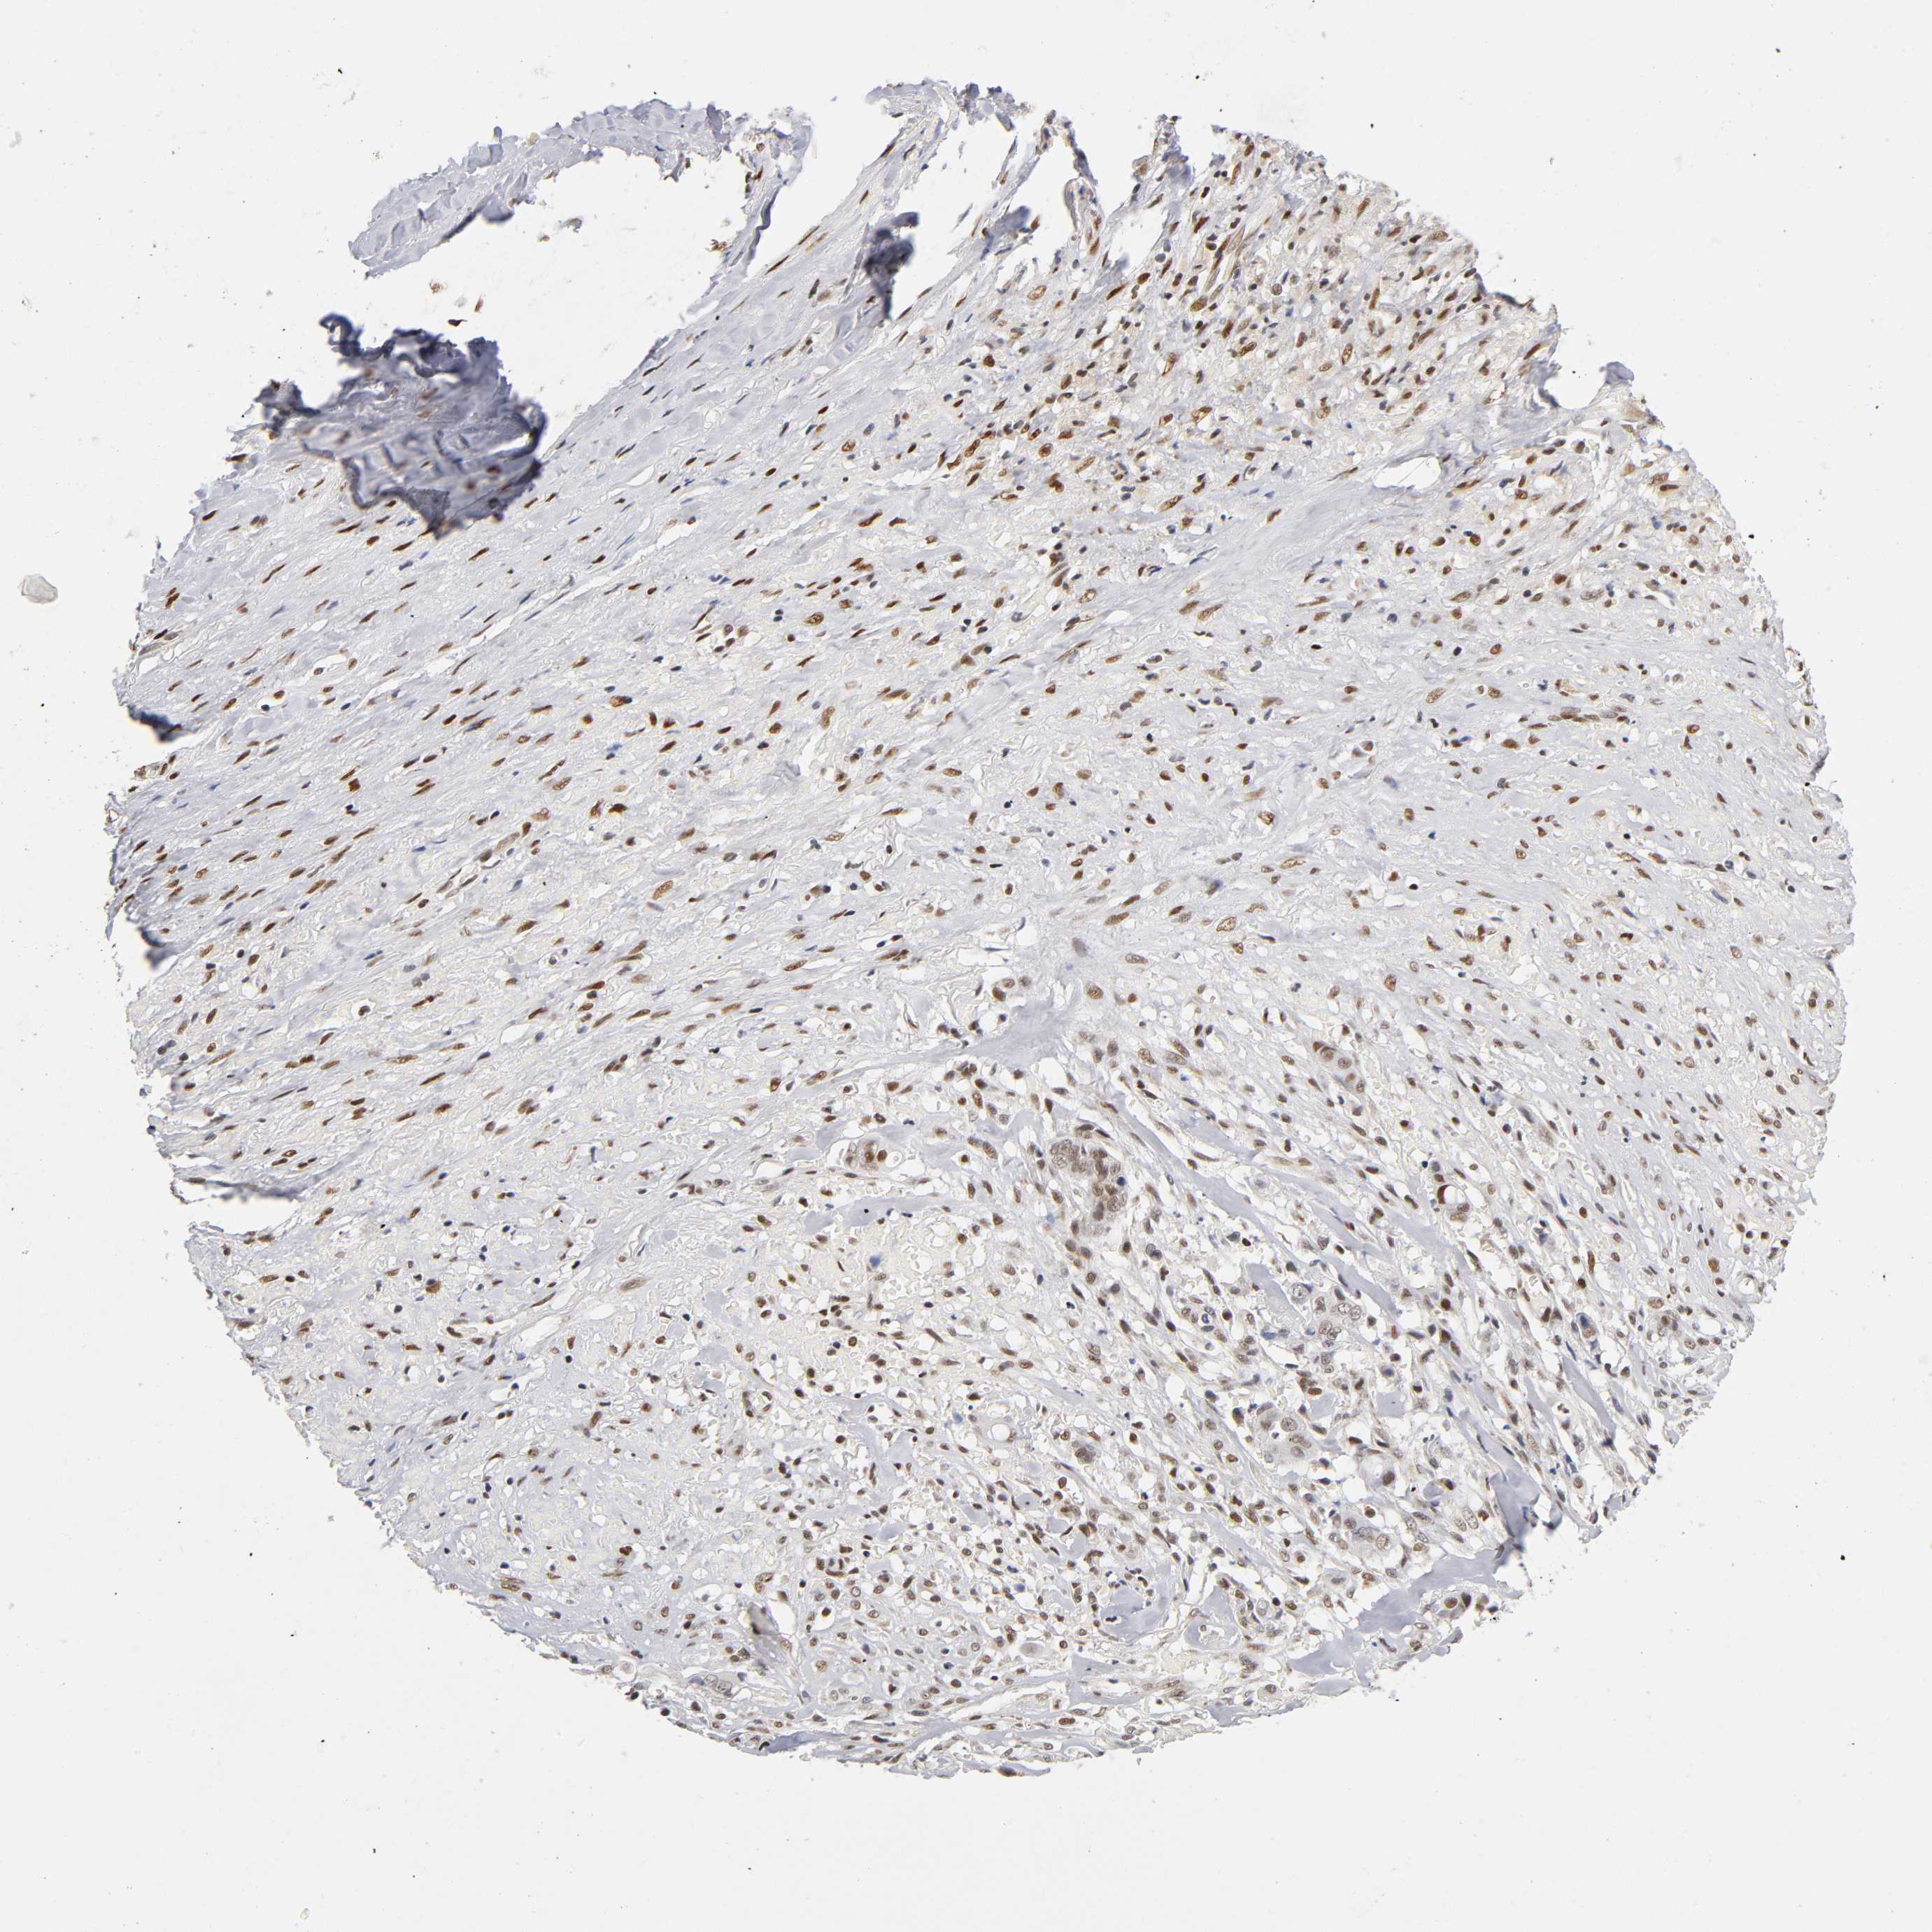

LIVER CANCER - Protein expressioni

A mouse-over function shows sample information and annotation data. Click on an image to view it in a full screen mode. Samples can be filtered based on level of antibody staining by selecting one or several of the following categories: high, medium, low and not detected. The assay and annotation is described here.

Antibody stainingi

Antibody staining in the annotated cell types in the current human tissue is reported as not detected, low, medium, or high, based on conventional immunohistochemistry profiling in selected tissues. This score is based on the combination of the staining intensity and fraction of stained cells.

Each image is clickable and will lead to virtual microscopy that enables deeper exploration of all samples and also displays staining intensity scores, fraction scores and subcellular localization as well as patient and tissue information for each sample.

Antibody HPA004248

Antibody CAB010435

Staining

High

Medium

Low

Not detected

Intensity

Strong

Moderate

Weak

Negative

Quantity

>75%

75%-25%

<25%

None

Location

Nuclear

Cytoplasmic/membranous

Cytoplasmic/membranous,nuclear

Cholangiocarcinoma

Carcinoma, Hepatocellular, NOS